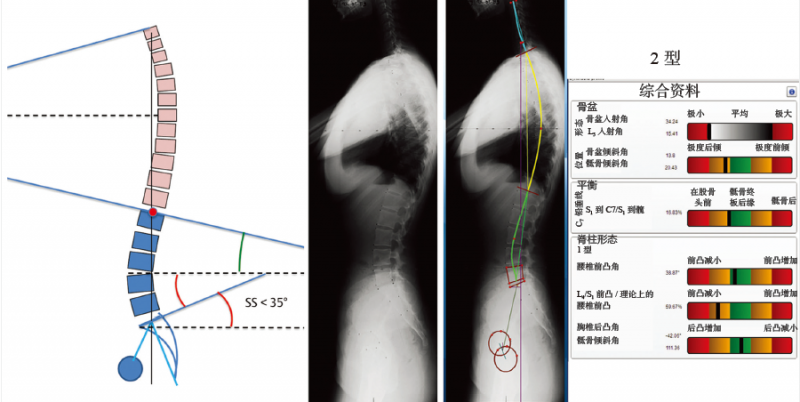

2型脊柱前凸(图6-11):特征在于骶骨倾斜角较小(<35°);腰椎前凸的顶点位于L4椎体;临界点更高且更靠前,腰椎前凸(超过个节段水平)接近一条直线;整个脊柱的前凸及后凸均不明显;背部相对平坦。

图 6-11 2型脊柱前凸

骶骨倾斜角<35°,临界点越来越高,越来越前,形成一个较长但平坦的下脊柱前凸(超过3个节段水平),接近一条直线,前后凸均较小。背部平坦协调